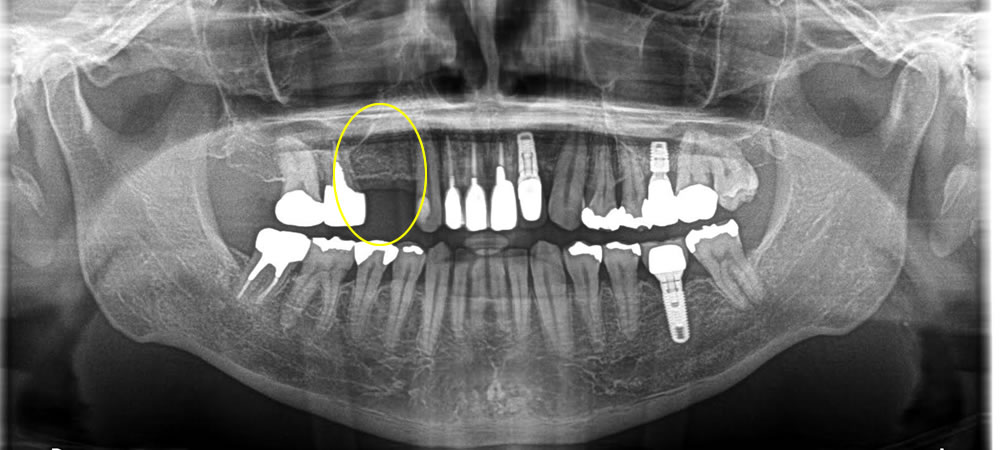

他院で抜歯した部分をインプラントで治療した症例

年齢

50代

性別

女性